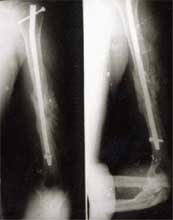

股骨骨折,钢板固定后失败。改用带锁髓内钉固定,4个月后骨折愈合。